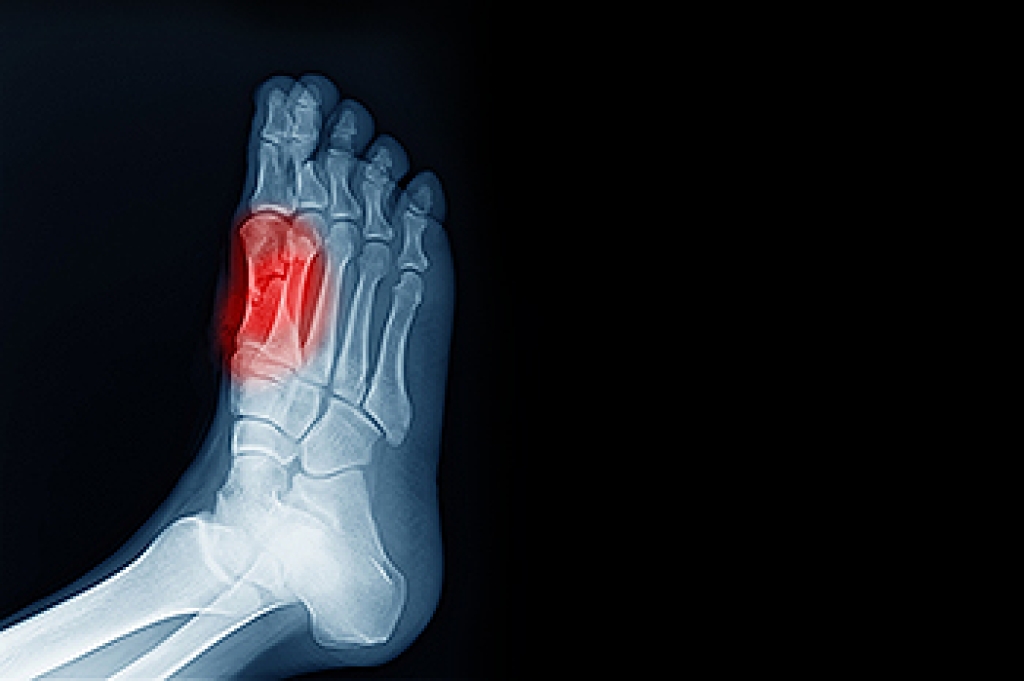

Gout is a form of arthritis that is characterized by sudden, severe attacks of pain, redness, and tenderness in the joints. The condition usually affects the joint at the base of the big toe. A gout attack can occur at any random time, such as the middle of the night while you are asleep.

- Intense Joint Pain - Usually around the large joint of your big toe, and it most severe within the first four to twelve hours

- Inflammation and Redness -Affected joints may become swollen, tender, warm and red

- Limited Range of Motion - May experience a decrease in joint mobility